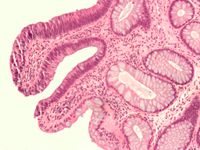

علم الأمراض